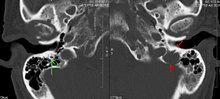

The most common cause of kidney failure in multiple myeloma is due to proteins secreted by the malignant cells. Myeloma cells produce monoclonal proteins of varying types, most commonly immunoglobulins (antibodies) and free light chains, resulting in abnormally high levels of these proteins in the blood. Depending on the size of these proteins, they may be excreted through the kidneys. Kidneys can be damaged by the tubulopathic effects of proteins or light chains. Increased bone resorption leads to hypercalcemia and causes nephrocalcinosis, thereby contributing to the kidney failure. Amyloidosis is a distant third in the causation. Patients with amyloidosis have high levels of amyloid protein that can be excreted through the kidneys and cause damage to the kidneys and other organs.

Micrograph showing myeloma cast nephropathy in a kidney biopsy. Hyaline casts are PAS positive (dark pink/red - right of image). Myelomatous casts are PAS negative (pale pink - left of image). PAS stain.